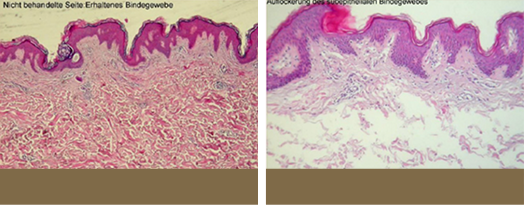

LDM

고밀도 초음파 에너지를 이용하여 콜라겐 자극과 섬유 조직의 타이트닝

동시에 유도하여 주름을 개선하고 피부 탄력을 증가시킵니다.